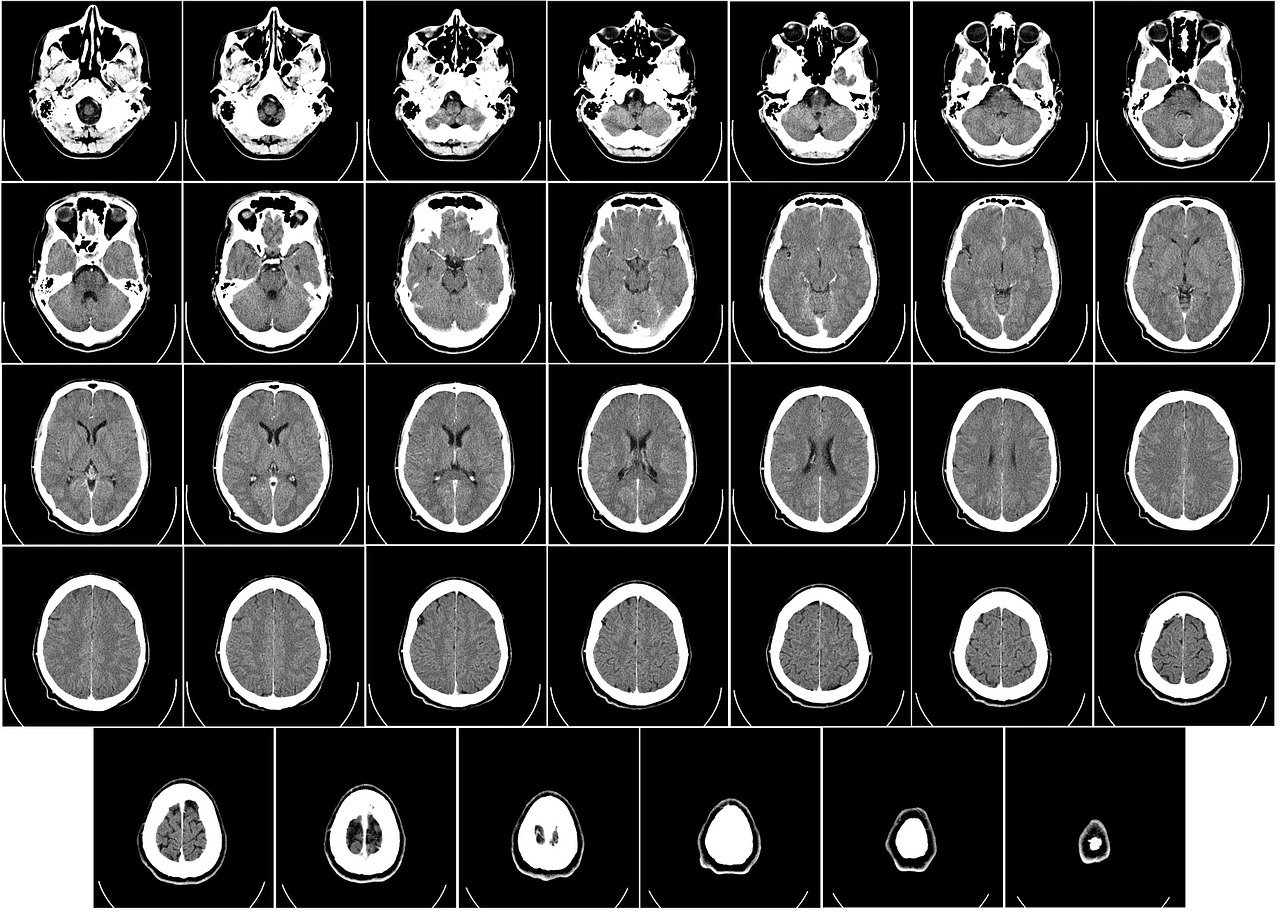

두개골은 윗부분은 뇌를 담은 커다란 두개강 cranial cavity로 되어 있고, 두개강 아래에는 안구를 담은 눈오목(안와) optic fovea 사이에 넓은 비강 nasal cavity가 있습니다. 또한 비강을 감싼 뼈의 속 부분에는 부비동 paranasal sinus라 일컫는 공간이 있는데 모두 비강과 연결되어 있습니다.

두개강 cranial cavity, 눈오목(안와) optic fovea, 비강 nasal cavity, 부비동 paranasal sinus, 유달동과 유돌벌집 mastoid sinus and mastoid air cell로 구분할 수 있습니다.

두개강 cranial cavity

뇌두개골( 전두골 frontal bone, 두정골 parietal bone, 후두골 occipital bone, 측두골 temporal bone, 접형골 sphenoid bone, 사골 ethmoid bone)에 감싸인 넓은 강 cavity입니다.

아랫면은 앞, 중간, 뒤의 3개 두 개 우묵을 형성합니다. 3개의 두 개우묵은 앞에서 뒤로 차례로 깊어져 있고 각 두 개 우묵(두 개와) cranial fossa는 아래와 같은 뼈로 이루어져 있다.